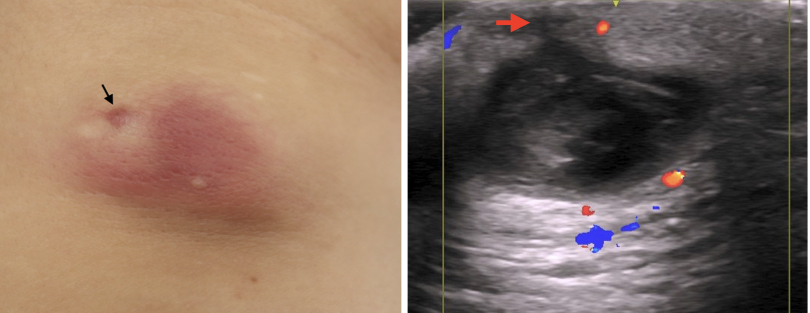

今回の症例も頚部の粉瘤腫で、くりぬき法を行います。

いつものように、くり抜き法で20分以内に終了するぞ!と思いきや、今回はやや慎重にならざるおえません

なぜなら恐怖のErb's pointが近くにあるからです

これは、教科書の写真ですが、胸鎖乳突筋中間(Erb's point)あたりから下斜めにspinal accessory nerve(副神経)がむき出しになって走っています。これに触ると腕があがらなくなります

消毒&局所麻酔後に、いつものように4mmトレパンで穴をあけます。

腫瘍の袋も絞り出されました。できるだけまわりの組織に触れないように袋を取り出します。慎重に!

最後は縫合して軟膏をぬって終了です。縫わなくてもいいんですが、今回も縫った方がきれいになりそうで縫いました。腕の麻痺が無いかチェックすることも大切です。でも、結局15分程度で終わっちゃいました![]()